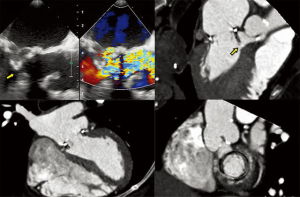

- TMVR relies on both echocardiography and CT, which are critical for patient selection, complete anatomic definition of the mitral complex, prediction of LVOT obstruction and complications diagnosis. Echocardiography is essential for procedural guidance (18,19,21,24,26,33-35). The transseptal puncture site is chosen to allow positioning of the device coaxial with the MA trajectory. A landing zone is chosen under fluoroscopic and echocardiographic guidance, monitoring for evidence of LVOT obstruction. 3D TEE is used to document full deployment of the atrial skirt and color Doppler helps detect perivalvular leaks. Sequential 2D X-plane views ascertain full leaflet capture by the device anchors, tabs or paddles, as TMVR devices do not rely on radial force for fixation. For apical delivery of TMVR devices, the location of left ventricular apical puncture is located by real time echocardiography as the operator “pokes” the ventricular apex, to identify a delivery trajectory coaxial with the MA trajectory (Figure 1) (14). TMVR procedures are divided in three categories: valve-in-valve, valve-in-ring, and valve-in-MAC (Figures 10-12, Video 4).